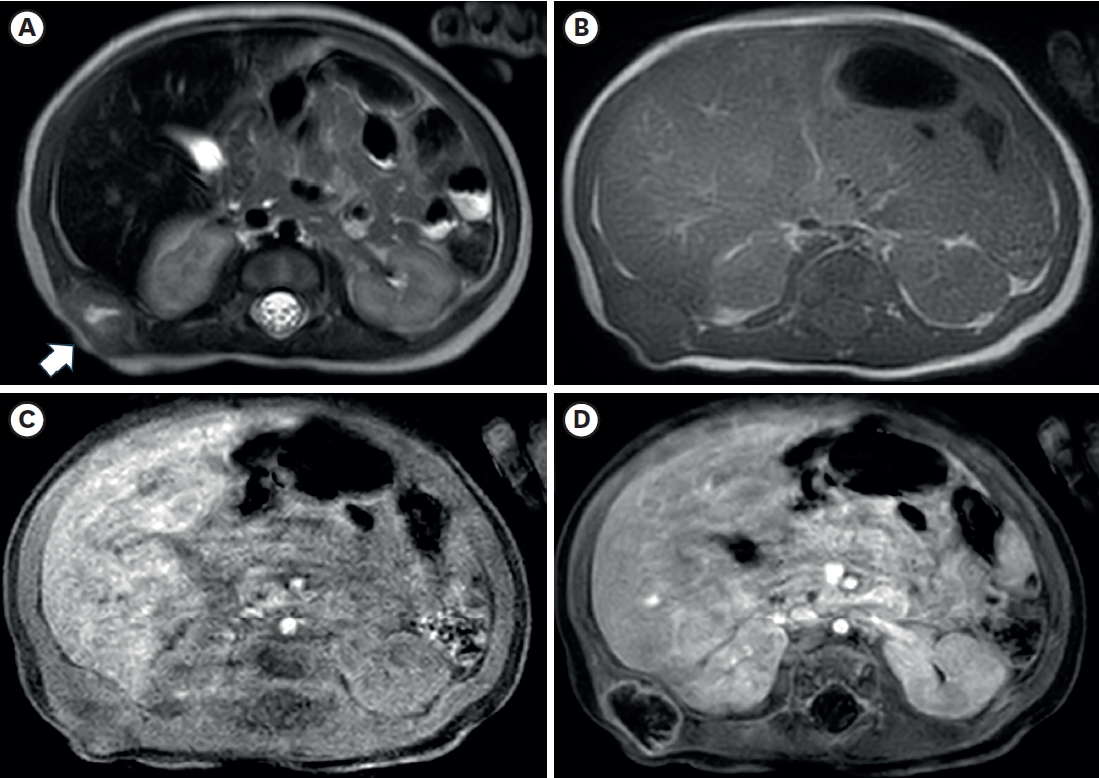

Fig. 1.

Ultrasonography of the right flank palpable lesion. (A) A lobulated soft tissue lesion (arrow) and is connected with (arrowhead) the muscular layer of the body wall, just outside of the RK and L, with an internal necrotic hypoechoic portion. (B) Doppler study shows increased vascularity in the mass lesion’s peripheral portion and surrounding areas.

RK, right kidney; L, liver.

A 3.3 kg female baby was born at 39 weeks gestation with a mass on the right chest wall, and she was admitted to the hospital. Except for the mass, the patient was healthy and had no comorbid diseases such as congenital anomalies. The mass was approximately 3 cm long, hard, fixed, and well defined, with no symptoms such as pain or skin changes. The ultrasound (US) examination (

Fig. 1) showed a lobulated soft tissue lesion in the muscular layer, with an internal necrotic hypoechoic portion. Magnetic resonance imaging (MRI,

The radiologic findings of PM are also not specific [

11]. In this case, the preoperative US showed internal hypoechoic lesions, and the MRI also showed an internal hyperintense portion on the T2-weighted image, which suggested internal necrosis. These lesions were proven to be central degeneration without hemorrhage or necrosis. These findings have not been reported previously, and they could be one of the possible radiologic findings of PM.